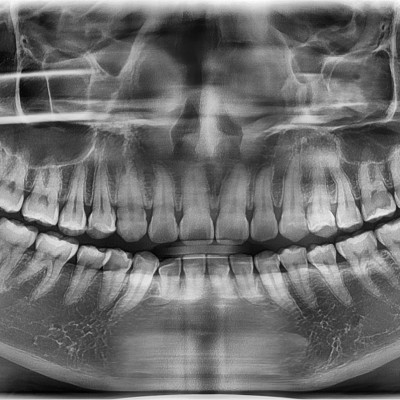

#28,38 사랑니 발치 #28,38 사랑니 발치 구강 외과 전문의가 당일 발치했습니다. ------------------------..

작성자 이턱이 작성일 02-11 조회 53